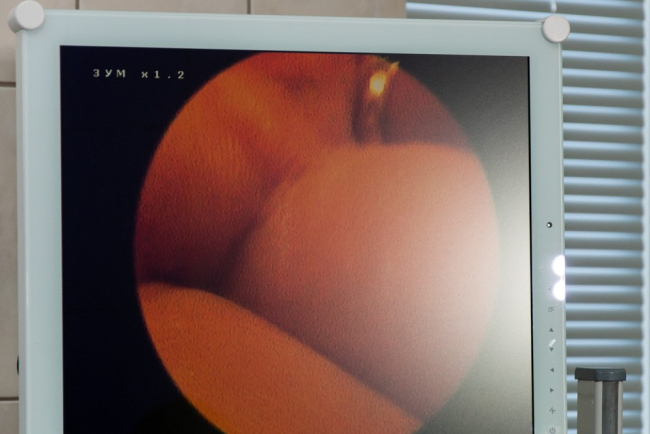

Также с недавнего времени в РКБ функционирует артроскопический комплекс. Его появление в Приднестровье врачи уже назвали прорывом в ортопедии. Современное оборудование позволяет поднять на качественно иной уровень диагностику и некоторые виды операций на суставах.

«Теперь нет необходимости делать большие разрезы, операция осуществляется из двух небольших разрезов, примерно 0,5 см, мы уже провели 10 артроскопий – операций – пациентам с острой травмой, послеоперационный период прошёл гладко», – рассказал врач травматолог-ортопед Александр Гаря.

Как подчёркивают в Минздраве, самое главное, что даёт такое оборудование, – это возможность для пациентов, страдающих патологиями суставов, пройти диагностику и лечение на территории республики, не выезжая за её пределы.